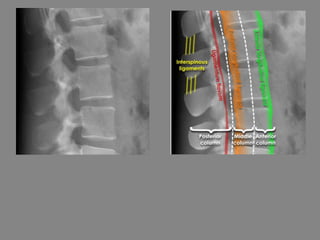

Three column model

• The Clinico-radiological assessment of thoracolumbar

spine stability is usually performed by spinal surgeons

with the help of radiologists.

• A simple model commonly used for assessment of

spinal stability is the 'three column' model. This states

that if any 2 columns are injured then the injury is

'unstable'. This theory is an over simplification if

applied to plain X-rays alone. It is important to be

aware that some injuries are not visible on X-ray and

that 2 and 3 column injuries may be underestimated as

1 or 2 column injuries respectively.

• If spinal instability is suspected on the basis of clinical

or radiological grounds then further imaging with CT

should be considered.

Three column model - Anatomy

• Anterior column = Anterior half of the

vertebral bodies and soft tissues

• Middle column = Posterior half of the

• Posterior column = Posterior elements and

soft soft tissues

• Three column model - Fracture simulation

• Injuries 1 and 2 affect one column only and are considered 'stable'

• 1 - Spinous process injury

• 2 - Anterior compression injury

• Injuries 3 and 4 affect two or more columns and are considered 'unstable'

• 3 - 'Burst' fracture

• 4 - Flexion-distraction fracture - 'Chance' type injury